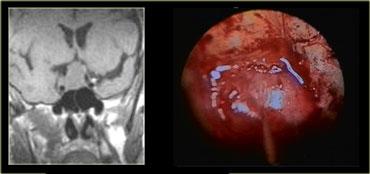

Các hình ảnh này mô tả phẫu thuật cắt bỏ u tuyến yên đại tuyến qua đường xuyên bướm (transsphenoidal resection).

Sau khi phần sàn xương của hố yên được lấy bỏ, màng cứng (dura) được rạch bằng đường rạch hình chữ thập.

Do áp lực phía trên màng cứng lớn hơn áp lực phía dưới, khối u đại tuyến sẽ tự thoát ra vào xoang bướm (sphenoid sinus).

Chụp MRI trong mổ được thực hiện trong một bối cảnh thử nghiệm để xác định xem phẫu thuật viên thần kinh có lấy bỏ thành công toàn bộ khối u hay không.

Do việc sử dụng đường phẫu thuật này có trường nhìn hạn chế, điều quan trọng là phải biết trước mình đang phẫu thuật trên tổn thương gì.

Như chúng ta sẽ thấy, có những tổn thương mà bạn không nên phẫu thuật theo đường tiếp cận này!